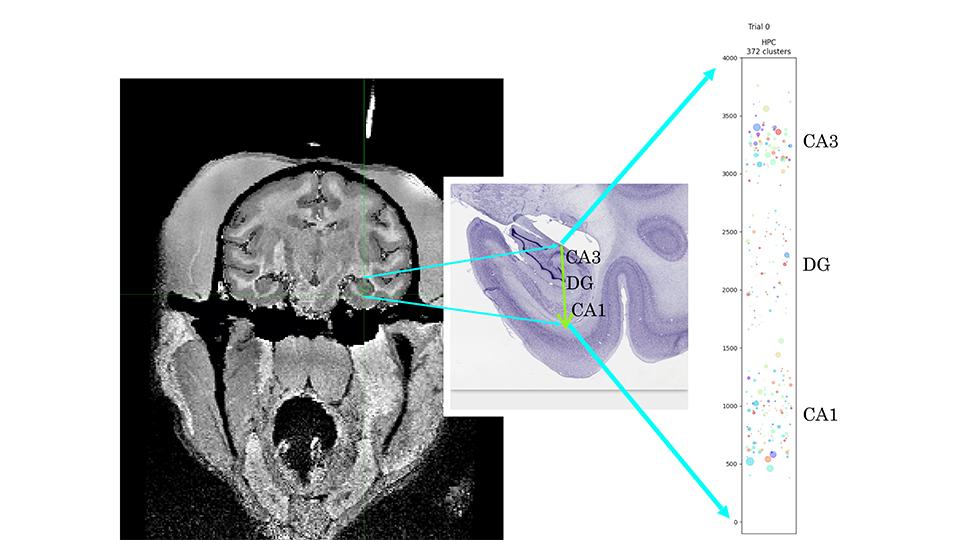

Neuroscientists have traditionally characterized neuronal response selectivity to reveal how the brain represents emotional states. For instance, neurons in basolateral amygdala (BLA) respond selectivity to positive and negative valence. However, emotions involve more than valence, and it is unclear how BLA encodes all relevant variables. If each neuron encodes one variable, then readouts of different variables would not interfere with each other, and readouts would also generalize across conditions. But can these computational properties be realized if neurons lack specialization? We tested this by presenting stimuli to mice that elicited two responses: tremble and ingress into a burrow, reflecting fear and flight to safety. BLA inactivation eliminated differential responses to aversive and neutral stimuli without eliminating responses themselves, suggesting BLA signals valence, not motor commands. However, two-photon imaging revealed that neurons exhibit mixed selectivity for stimulus identity, valence, tremble and/or ingress. Despite this, BLA population activity represented valence, tremble and safety within low-dimensional geometries, reflecting linear mixed selectivity and enabling generalization across conditions. Further, tremble and valence coding directions were orthogonal, eliminating interference between readouts. Thus BLA can achieve specialized readouts of variables describing emotional states with particular representational geometries, not requiring neurons with specialized selectivity.